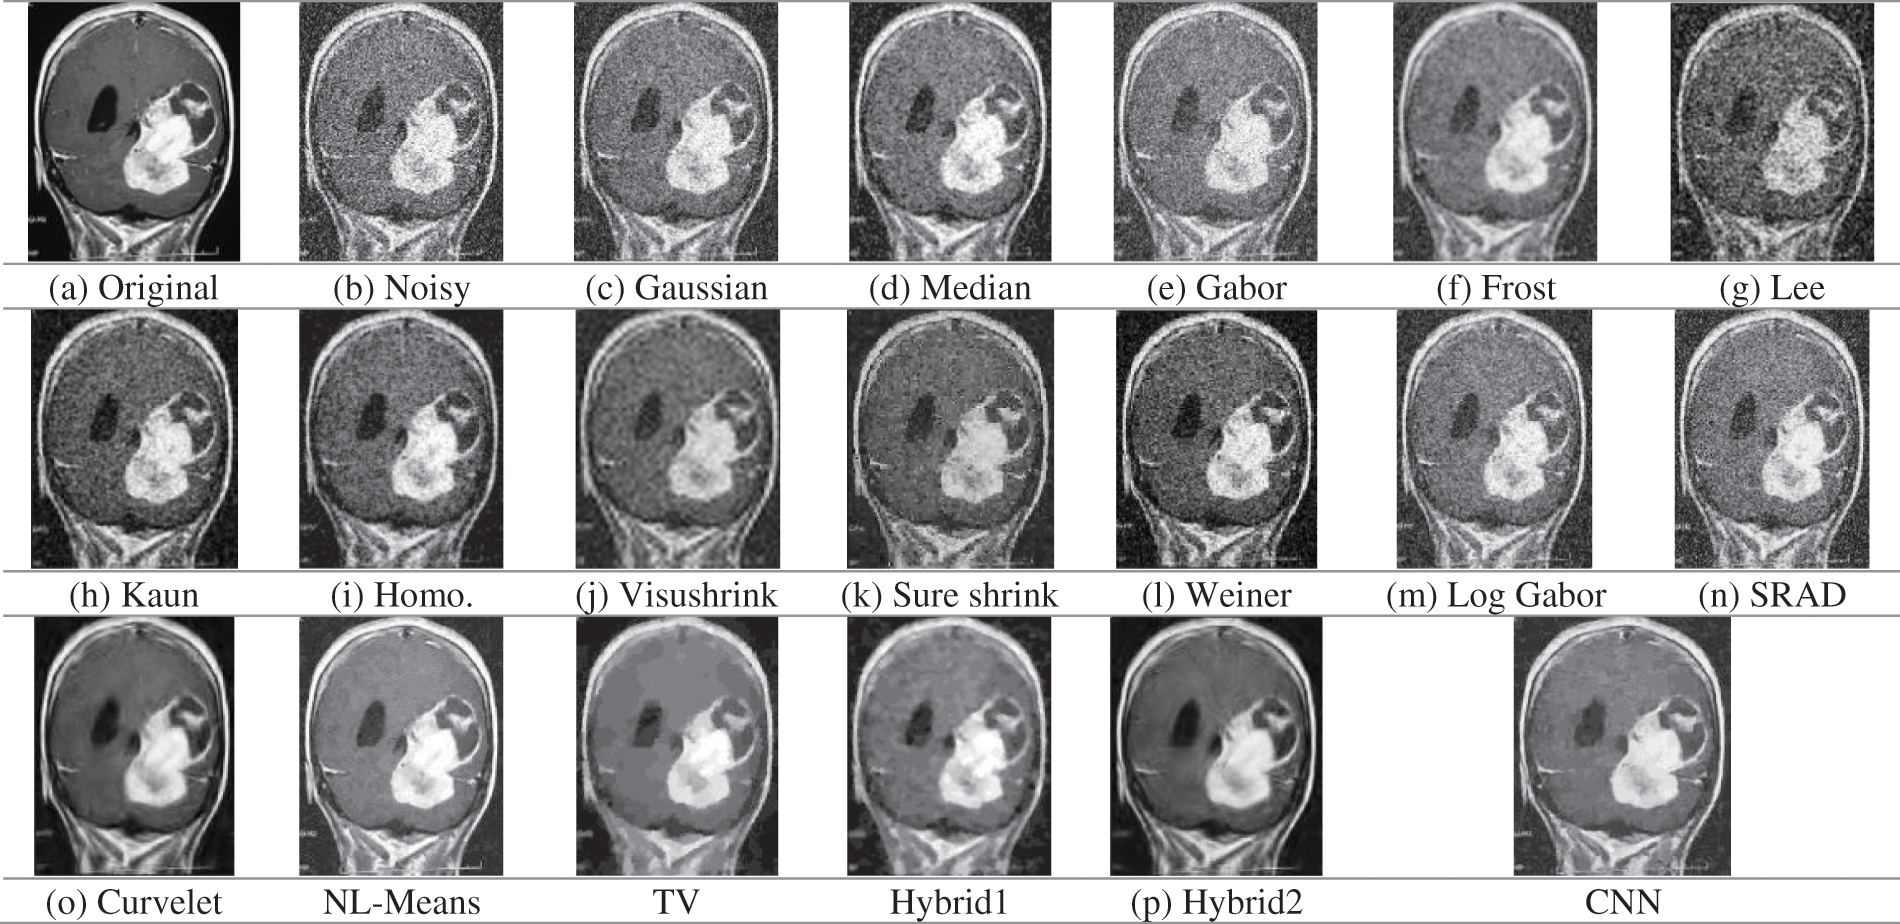

Figure 7: Obtained outcomes for the examined denoising filters for the MRI image at 0.05 gaussian variance

Fig. 7 shows the original, noisy, and denoised output images of the MRI brain images. The MRI image, shown in Fig. 7a, has different regions, great details, smooth white, and dark regions with fine details. It is obviously shown in Fig. 7b that the noise severely degrades the image quality. Gaussian, median, Gabor, Lee, Weiner, Log-Gabor, and SRAD filters poorly deal with the image noise, and residual noise and the artifacts still exist. Wavelet-based techniques, visushrink, and sure shrink, smooth the image and affect the contrast heavily. Moreover, the Frost, Curvelet, and hybrid2 output results are blurred seriously. Fig. 7 shows the perceptual and visual superiority of the NL-Means and CNN models over the rest of the models.

The CNN model for Gaussian noise reduction excels from the MRI image in Tab. 5. The Cr values of hybrid2 and the CNN model are higher than hybrid1 and the TV techniques with lower Cr values. It is noticed that the CNN model is more efficient to denoise multimodal medical images with different noise types at low, medium, and high noise variances. As a result of using deep residual learning, the proposed model outperformed CNN by separating noise from noisy images.